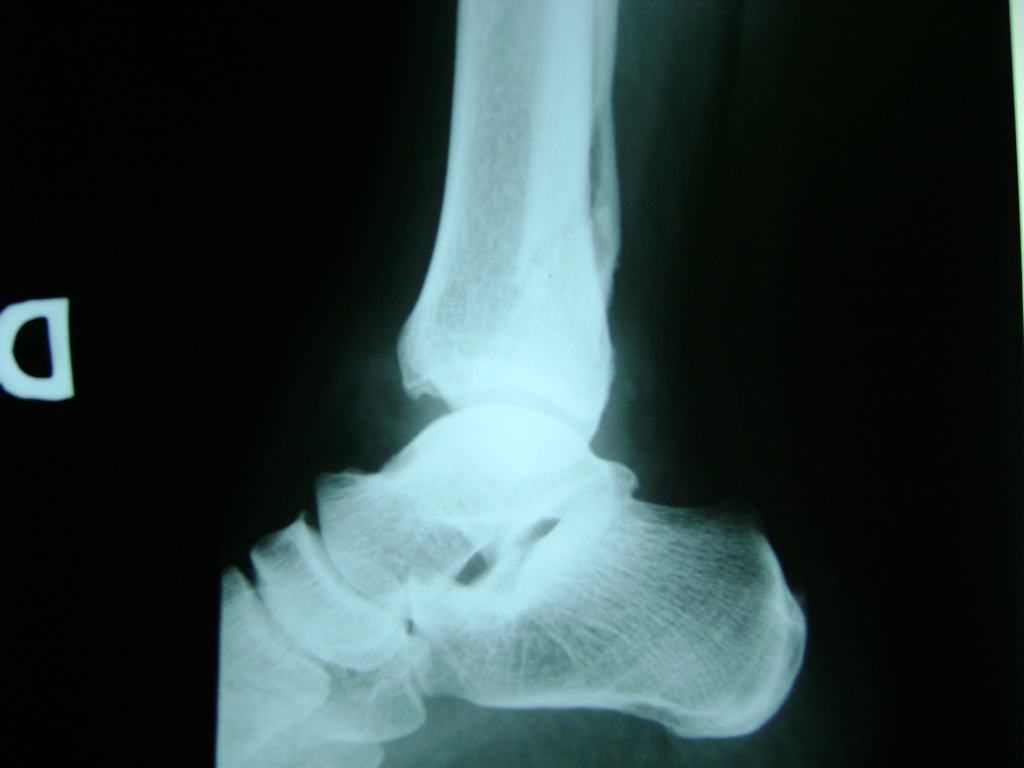

Una fractura de tobillo es la rotura de uno o más de los huesos del tobillo. Estas fracturas pueden ser:

Algunas fracturas de tobillo pueden requerir cirugía si:

- Los extremos de los huesos están desalineados entre sí (desplazados).

- La fractura se extiende hasta la articulación del tobillo (fractura intra-articular).

- Los tendones o ligamentos (tejidos que sujetan los músculos y los huesos entre sí) están rotos.